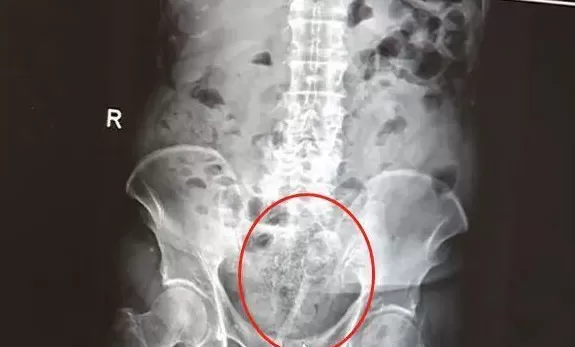

急诊科医生快速检查后,倒吸了一口凉气:直肠粘膜被捅破,血流不止,粪便污染引发局部感染,出血速度已经接近失血性休克的临界值!

急诊科医生立即对王伯进行抗失血性休克治疗,经过开通静脉通路、补液、输血等一系列抢救措施,维持住了王伯的生命体征。

但因王伯本身患有高血压、慢性心功能不全、肾功能不全等多种基础疾病,这一意外无疑雪上加霜。结直肠外科专家团队紧急出动,折腾了一个多小时,才成功止血。